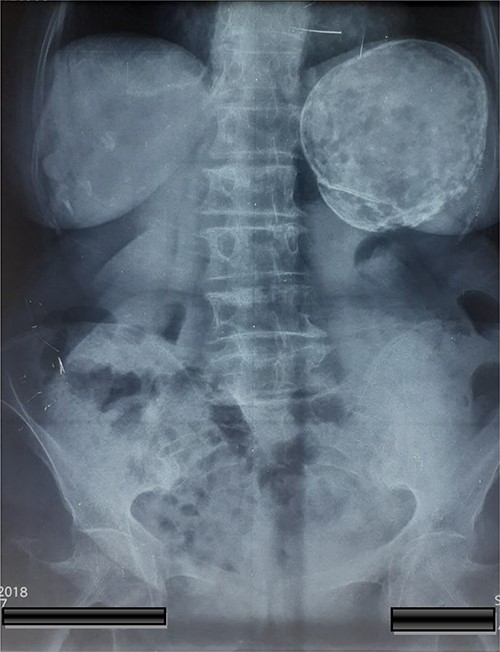

A 74-year-old woman was admitted to the internal medicine ward due to cough, pain and heaviness in the left upper abdominal quadrant. Pain was localized to the left upper abdominal quadrant, and it intensified within the last 2 months. The laboratory test results were normal. However, physical examination revealed tenderness upon palpation in the left upper quadrant and splenomegaly. Moreover, thoracic and abdominal radiography revealed an egg shell-like calcified well-circumscribed ovoid mass at the left upper abdominal quadrant (Fig. 1). Computed tomography (CT) scan of the abdomen revealed a 10.5 × 9.6 × 9.5-cm ovoid splenic cyst with peripheral rim calcification. The cyst had homogeneous internal substance with no prominent daughter cysts or scolices (Fig. 2). Thoracic and abdominal CT-scan did not reveal other pathologies and cystic lesions. The patient underwent exploratory laparotomy. Then, a splenic cyst was observed, and the spleen was found to be densely adherent to the diaphragm and gastrosplenic ligament. A laparotomy was performed and the spleen with the cyst was removed without opening. A well-described accessory spleen with a diameter of 8 mm was found in the gastrosplenic ligament. The splenectomy specimen and the accessory spleen weighed 320 g and 4 g, respectively (Fig. 3), and they were sent for histopathological examination. The patient’s postoperative recovery was uneventful. She was discharged on the sixth postoperative day and treated with albendazole for 3 months.

Abdominal X-rays with a calcified cyst at the left upper quadrant of the abdomen.